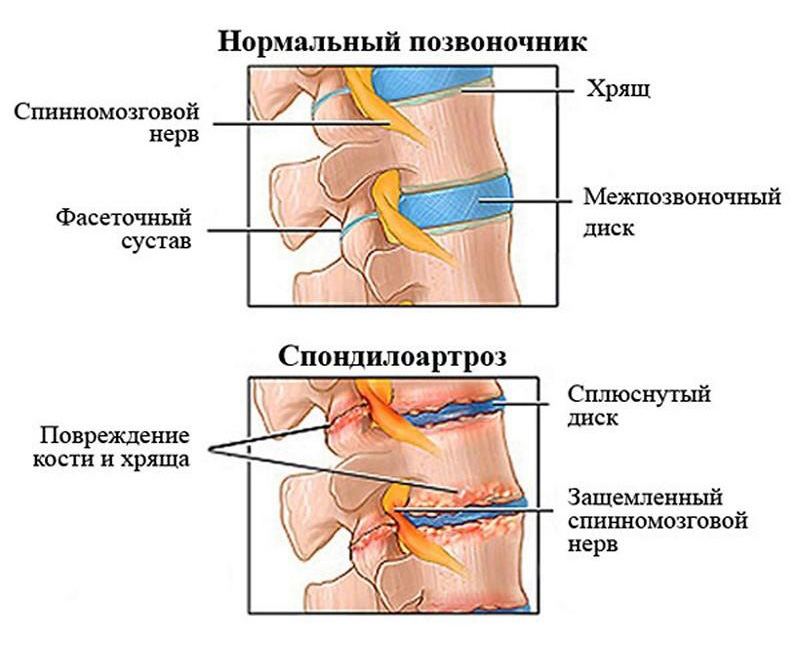

Позвонок Th10: анатомия и фото медицинских иллюстраций